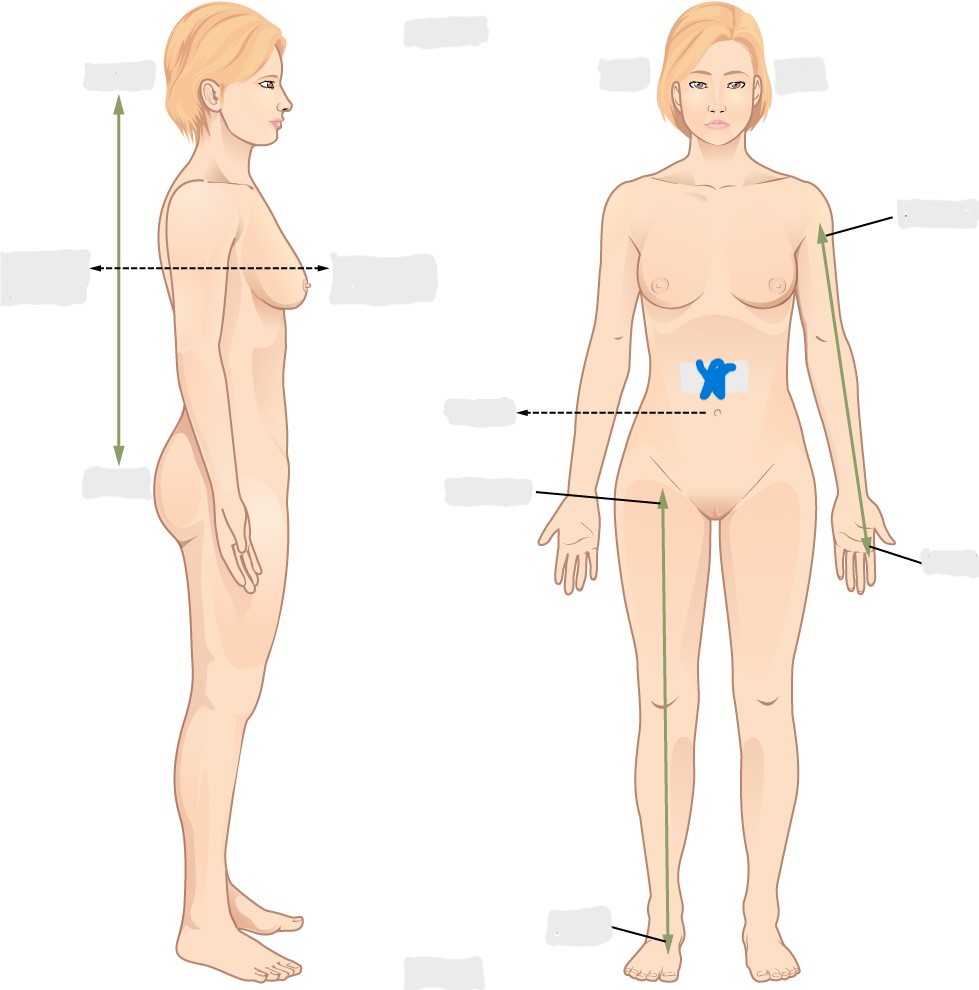

axial

appendicular

acromial

brachial

antecubital

olecranal

antebrachial

carpal

manus

coxal

femoral

patellar

popliteal

crural

sural

peroneal

calcaneal

plantar

sagittal plane

frontal/coronal plane

transverse plane

dorsal/posterior

ventral/anterior

lateral

medial

distal

proximal

superficial

deep

superior

inferior